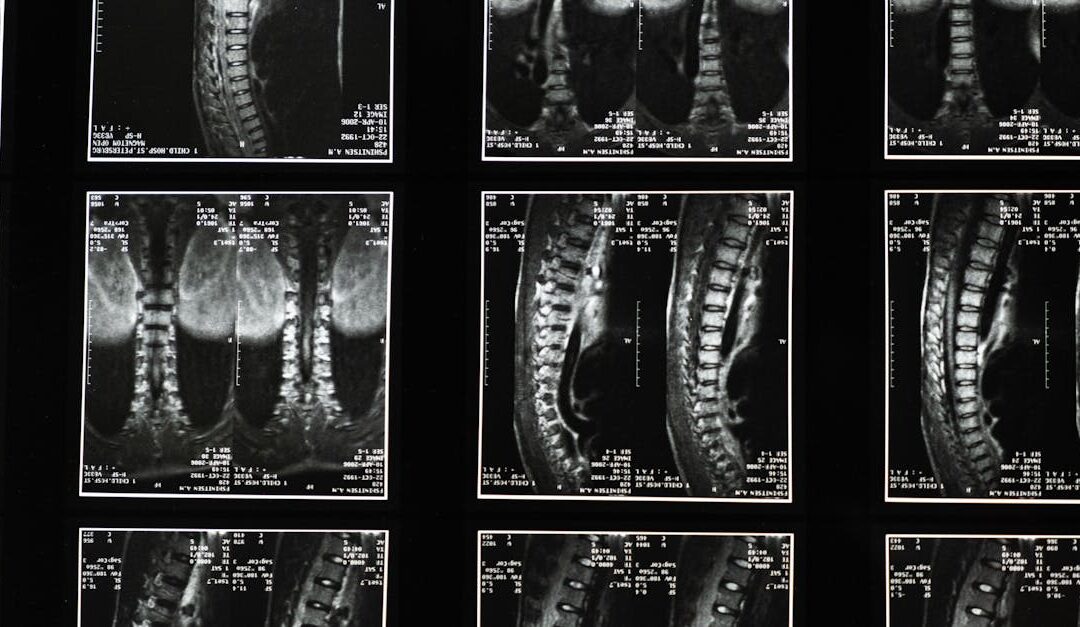

Spinal degeneration is a common concern as we age, but understanding what it means can help you stay active and comfortable. This guide is written for people in Clark, NJ who want practical, evidence-informed information about stages, risk factors, and chiropractic...

Whether you’ve recently heard the terms bulging disc or extruded disc, you’re not alone. Many people live with spine-related pain and want a clear, practical explanation of what these terms mean and how they affect daily life. This article is written for patients in...

Whether you’re dealing with a sharp, shooting pain that travels from the lower back into the buttock or leg, or you notice numbness, tingling, or weakness with movement, sciatic nerve pain—often called sciatica—is a common concern. This article is written for people...